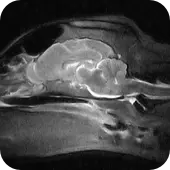

Obraz RM mózgu psa

Nowoczesny aparat Esaote zaadaptowany do badań w weterynarii (neurologia, ortopedia, diagnostyka guzów).

Obrazowanie 2D i 3D (RM trójwymiarowe) dla precyzyjnej analizy zmian chorobowych.